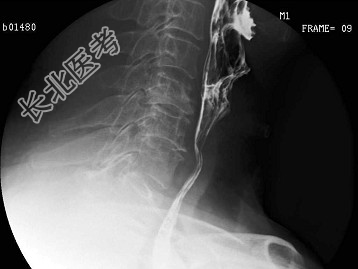

- 多项选择题男,64岁, 进食梗阻感半月。体检:咽充血少许滤泡, 结合图像,最可能的诊断为 ( )

A、会厌征

B、颈椎退变

C、食管癌

D、食管型颈椎病